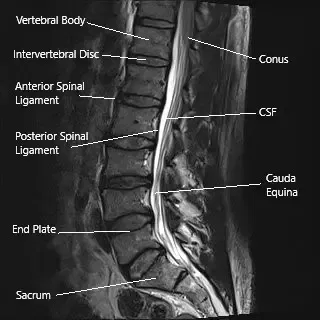

Sección sagital de la columna lumbar en una resonancia magnética.